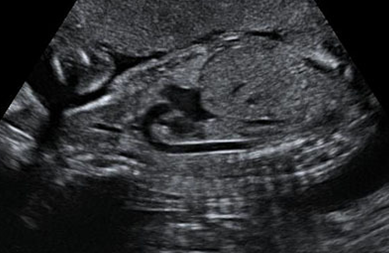

产科_胎心_三血管切面